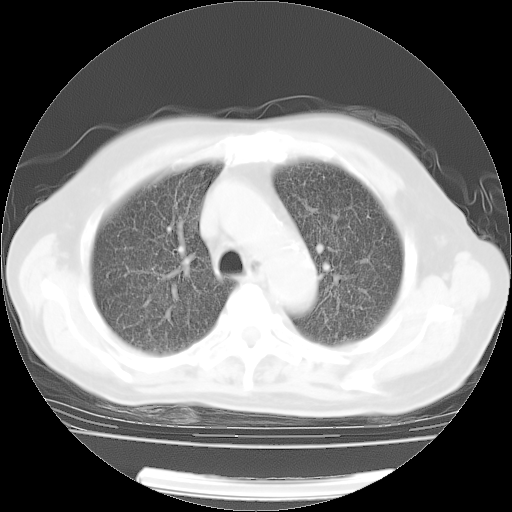

4月14日肺部CT

31.JPG

32.JPG

33.JPG

34.JPG